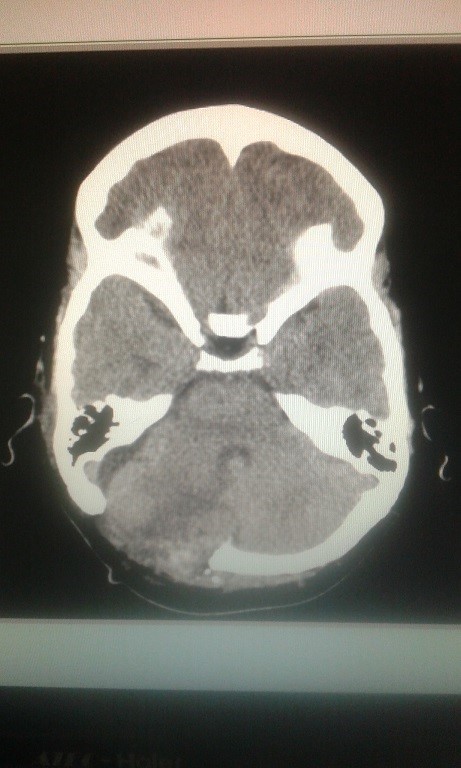

Volver a los detalles del artículo Meningioma incidental del tentorio